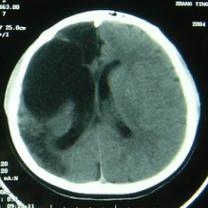

CT检查:右额部见边缘清晰的脑脊液密度区,大小约82mm×52mm,与侧脑室相沟通,内侧达中线,其内可见带状分隔;右侧颞顶叶及部分枕叶脑组织呈低密度改变,左侧侧脑室形态、大小正常,中线结构尚居中(图1)。

图1 CT(①②)显示右额部边缘清晰的脑脊液密度区与侧脑室相沟通,其内可见带状分隔;右侧颞顶叶及部分枕叶脑组织呈低密度改变